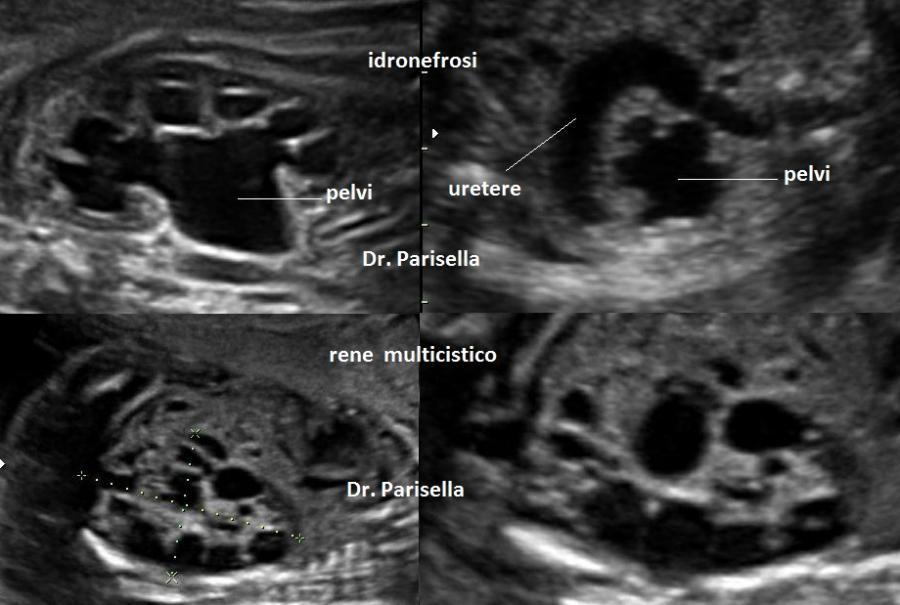

Il sospetto in diagnosi prenatale  ecografica si basa sul riscontro delle seguenti anomalie fetali:

5. displasia renale cistica